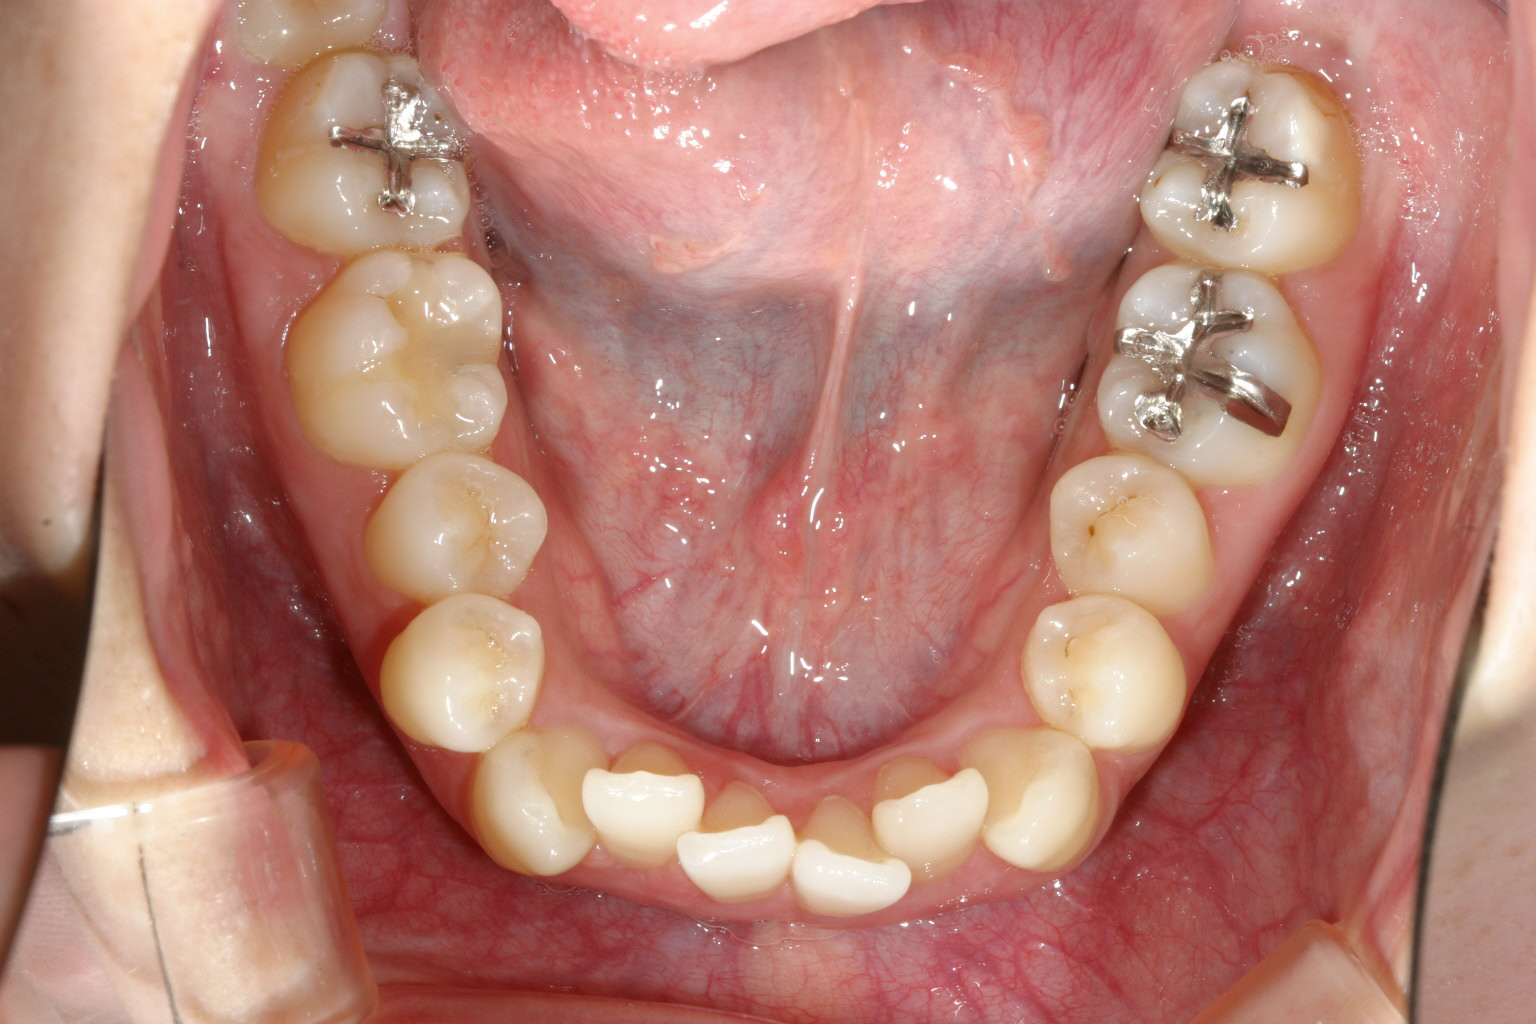

下顎も上と同じでアーチが狭いです。

下顎も上と同じように調整しました。